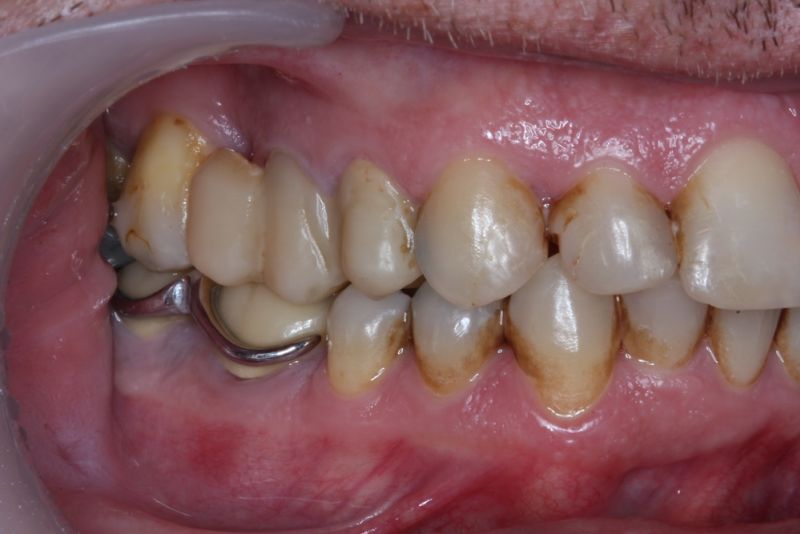

Erkennbar ist die massive Abweichung der habituellen Bisslage von der neuromuskulär zentrierten Bisslage.